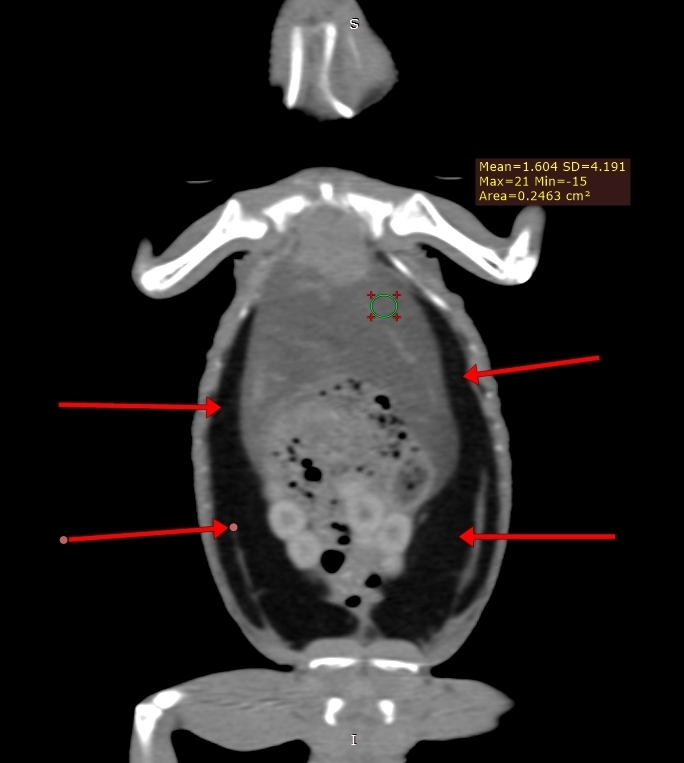

Компьютерная томография на сегодняшний день представляет собой наиболее информативный метод визуализации для диагностики липидоза печени у пресмыкающихся, включая ящериц2,12,13,19. Данный метод позволяет количественно измерять рентгенологическую плотность в единицах Хаунсфилда (HU), основываясь на поглощении рентгеновских лучей различными тканями8. Плотность печени менее 20 HU коррелирует с наличием умеренного липидоза печени у бородатых агам и других видов ящериц2,7 (фото 1-3) . Компьютерная томография оказалась высокоточным методом диагностики липидоза печени у бородатых агам как с умеренной, так и тяжелой степенью заболевания. Была выявлена линейная корреляция между плотностью печени, измеренной в единицах Хаунсфилда, и результатами гистологического анализа образцов печени. Увеличение содержания жира в печени на 10% соответствовало уменьшению плотности печени на 4 HU2.